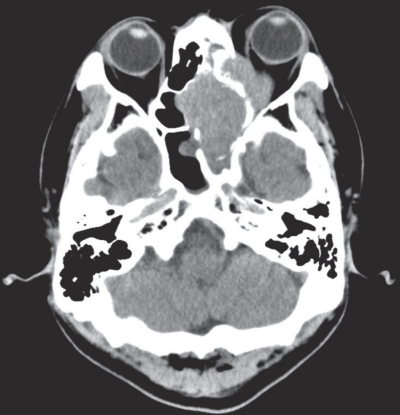

69歳の男性。左鼻出血と複視を主訴に来院した。1か月前から左鼻出血を繰り返し、徐々に左鼻閉が悪化した。2日前から物が二重に見えることを自覚した。副鼻腔の造影CTと造影MRIとを別に示す。左鼻腔生検で扁平上皮癌を認めた。

脂肪抑制造影T1強調冠状断像